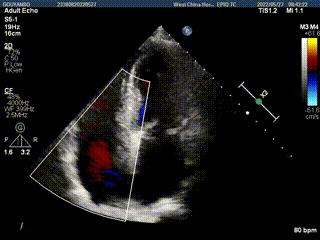

89岁男性。术前超声报告显示:双房增大,左室壁肥厚,主、肺动脉增宽,三尖瓣重度反流。

术前超声

术后超声